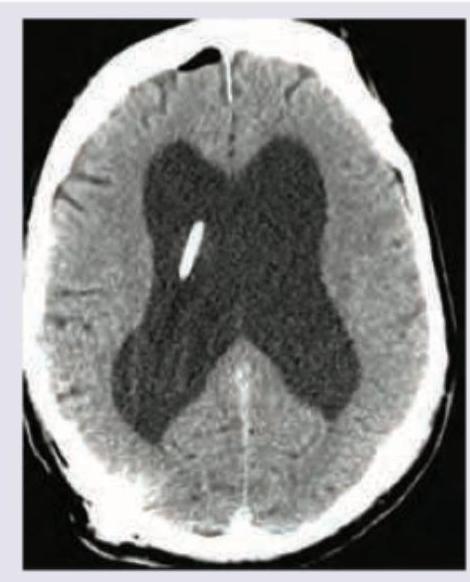

Explanation: ***Pneumocephalus*** - The image clearly shows a **dark, hypodense collection** within the subdural space, anteriorly, which is characteristic of air - This finding, combined with the presence of a metal clip, often indicates **post-surgical air entrapment** or a **breach of the dura mater** - Pneumocephalus appears hypodense (dark) on CT imaging due to the low density of air compared to brain tissue *Interventricular bleeding* - **Intraventricular bleeding** would appear as a **hyperdense (bright)** collection within the ventricles due to the presence of blood, which is not seen here - The ventricles are enlarged and dark, consistent with cerebrospinal fluid, not hemorrhage - Blood products are radiodense and would show as bright white areas on CT *Artifact* - While artifacts can occur on CT scans, the **well-defined, crescent-shaped hypodensity** with a characteristic appearance of air makes it an unlikely explanation for this specific finding - Artifacts typically present as streaks, rings, or other image distortions, rather than anatomically consistent gas collections - The systematic location and morphology of this finding is consistent with true pathology *Ventriculoperitoneal shunting* - Although a **shunt catheter** is visible within the ventricle, the primary and most striking finding is the **presence of air (pneumocephalus)** in the cranial cavity - The shunt itself is a device/procedure, not the pathological finding being demonstrated - The shunt is likely related to the cause of the pneumocephalus (post-procedural complication) rather than being the diagnosis itself